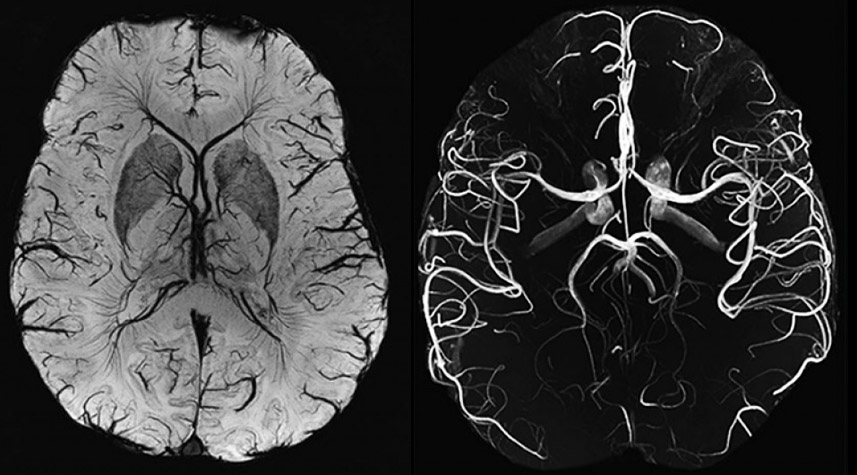

Медицинская диагностика: КТ и МРТ головного мозга